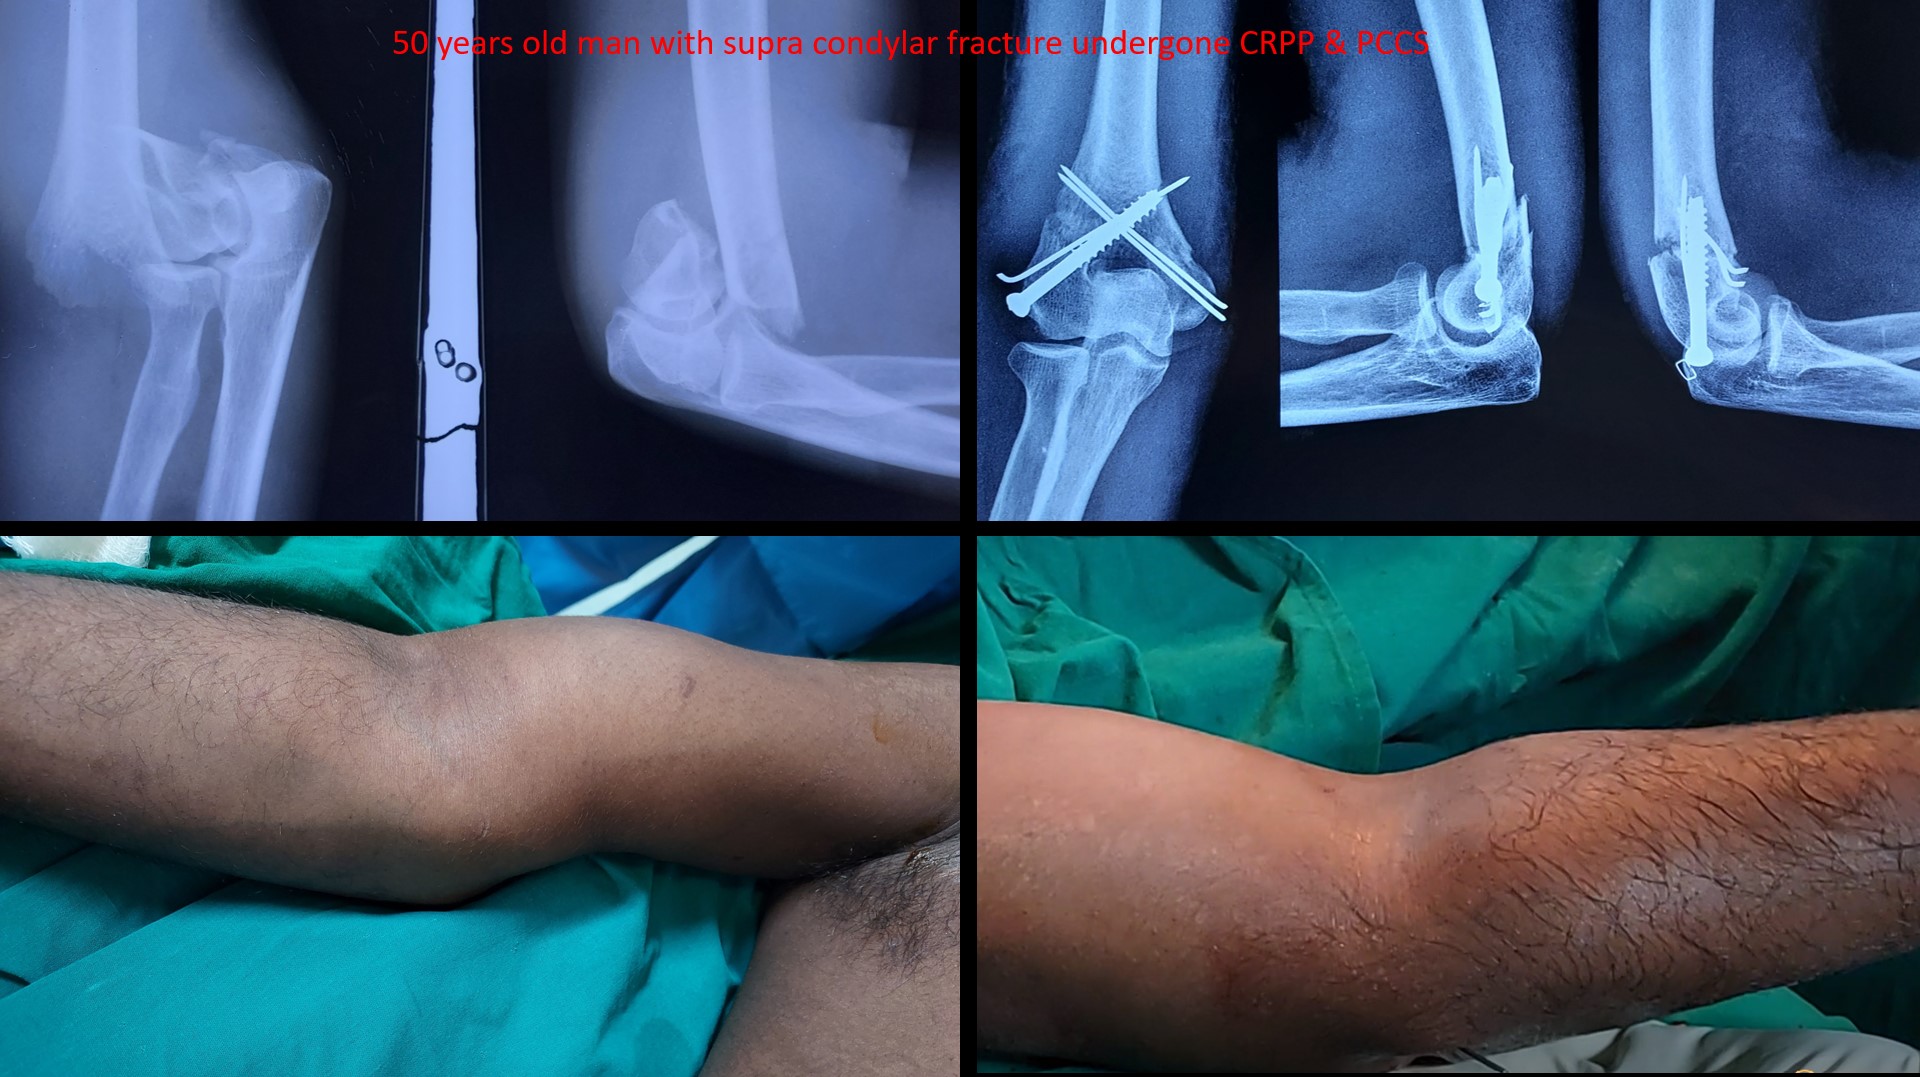

SUPRACONDYLAR #